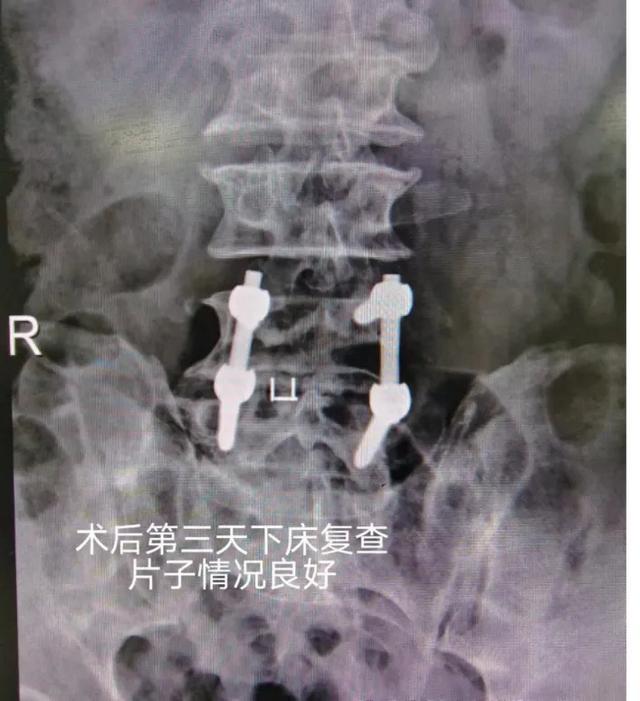

经科室梁剑主任、汤毅副主任医师诊疗后诊断为患者为严重腰椎间盘突出,引发马尾综合征,目前神经功能障碍,病情严重,为挽救患者的生活质量,在征得患者及家属同意后火速安排次日手术,术后恢复情况十分理想。家人非常满意!